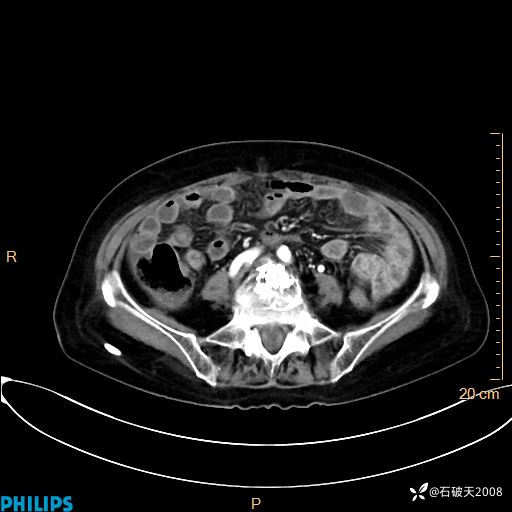

动脉期